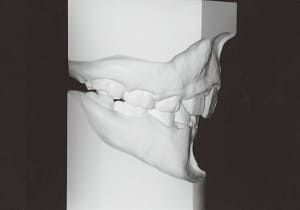

Age at initial visit : 7 y 7 m, male /Protruding upper bite. Open bite. Receding lower jaw. Protruding dual dentition.

The Class II condition is pronounced, with a significant overjet of 12.5 mm(3). Although the teeth size are large, crowding is relatively mild. The maxillofacial structure has good depth and a robust bone framework(5). The mandible itself is solid , robust gonial angle, but there is significant anterior-posterior displacement relative to the maxilla(ANB 10.0°). While there is no confirmed history of thumb-sucking or similar habits, the lower lip is already pushing up against the maxillary incisors. The cause of this condition is unknown.